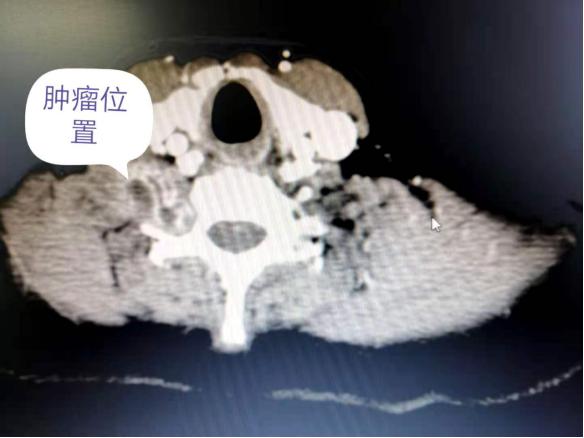

通过为患者李某某完善颈部增强CT及彩超等相关检查,提示患者右侧颈深部颈椎旁为实性肿块占位,考虑臂丛神经来源性比较大,肿块体型巨大,呈膨胀性生长并紧贴椎间孔,颈椎体、横突及椎弓根明显受压变形,颈椎体与横突间距明显扩大,臂丛神经干已经明显受压移位,所 以患者才会有右侧上肢、肩部麻木感及右侧上肢有部分活动受限。

术前患者影像资料